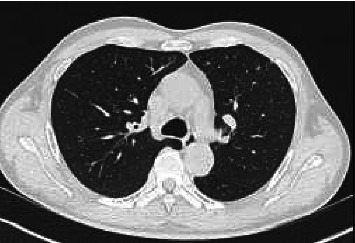

Chlamydia psittaci, the causative agent of psittacosis, is an intracellular bacterium typically transmitted from birds to humans, leading to atypical pneumonia. We present a case of a 60-year-old man with no reported bird exposure but a history of working as a chief cook, potentially exposed to poultry. He presented with high fever, diffuse soreness, and left-sided pulmonary consolidation. Initial treatment with β-lactams was ineffective, but a multiplex PCR on bronchoalveolar lavage identified C. psittaci DNA. Therapy was switched to moxifloxacin, resulting in rapid clinical improvement. C. psittaci causes approximately 1% of community-acquired pneumonias, often underdiagnosed due to nonspecific symptoms and the need for advanced diagnostic tools like nucleic acid amplification tests (NAATs) or metagenomic next-generation sequencing (mNGS). The bacterium is endemic in birds and poultry, with human infections linked to occupational exposure or contact with infected animals. Diagnosis relies on NAAT and mNGS, as serology and culture are less practical. Treatment with tetracyclines, quinolones, or macrolides is effective, reducing mortality from 10%-20% to < 1%. Preventive measures, including protective equipment for high-risk individuals and treatment of infected birds, are crucial. Mandatory reporting of cases could improve understanding of the disease burden. This case highlights the importance of considering psittacosis in atypical pneumonia, even without direct bird exposure, and the role of NAAT or mNGS in accurate diagnosis.

Abstract Image